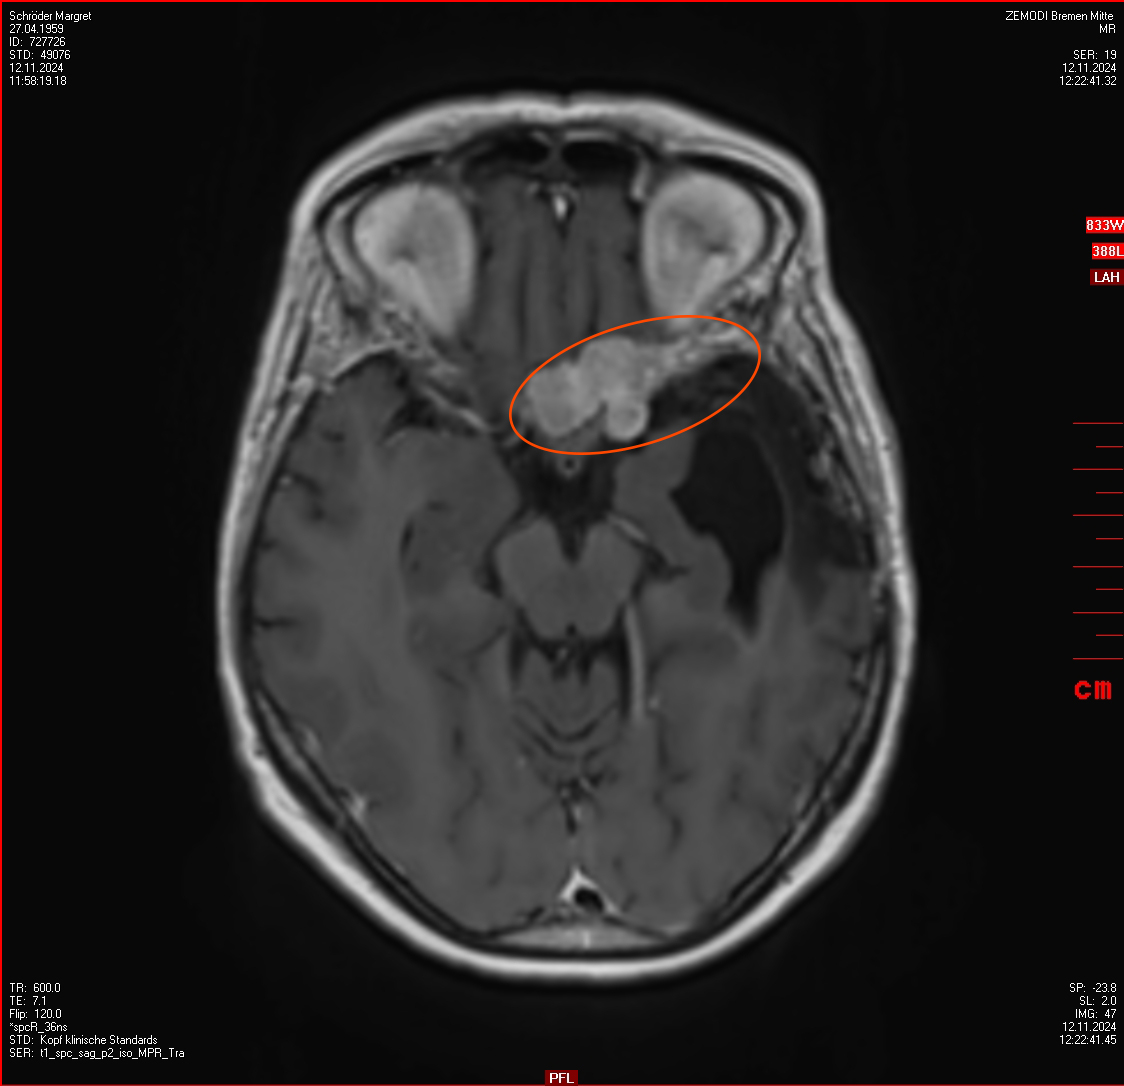

In der Ambulanz der Neurochirurgie im Bremen Krankenhaus-Mitte sind die Bilder interpretiert worden und es ist eine Behandlung nötig. Da wächst ein Menigeom ziemlich nah beim Sehnerv. Alles was im Bild markiert ist, gehört nicht dahin.

Die Tumorkonferenz empfiehlt zunächst eine erneute OP und diese Meinung teilt auch der Spezialist der Radiochirurgie aus Hamburg. Schön, dass man in einer recht kurzen Zeit einige Expertenmeinungen bekommt. Wenn das Ergebnis unterschiedlicher Personen und Instituionen übereinstimmt, dann habe ich ein ganz gutes Gefühl. Und ein Termin für die OP ist schon für die nächste Woche geplant. Danach wird man sehen ob weitere Behandlungen nötig sind.